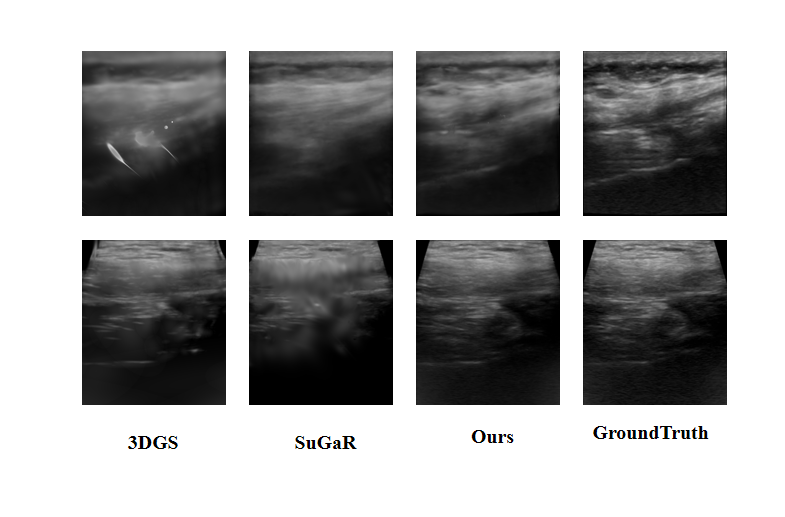

Refer to caption

Figure 4: Comparison of kidney sample visualization results from the Clinical Dataset

The visual comparisons in Fig. 3 and Fig. 4 provide additional evidence of these advantages. NeRF and Ultra-NeRF reconstructions are heavily degraded by noise and blurring artifacts, while 3DGS reconstructions exhibit noticeable structural misalignments. TensoRF and SuGaR generate sharper details but lack robustness across datasets, leading to inconsistent visual quality. In contrast, UltraGS produces reconstructions that better preserve anatomical boundaries, maintain sharper edge details, and achieve higher contrast, which are closer to the ground truth. This consistency across datasets and clinical cases underscores UltraGS’s effectiveness in capturing complex tissue structures while suppressing noise. More visual results can be found in the supplementary materials.

Performance on the Clinical Dataset is further summarized in Table 2, where UltraGS consistently outperforms competing methods across all six cases. While NeRF and Ultra-NeRF often suffer from blurred reconstructions with high noise, and 3DGS produces misaligned structures, our method maintains stable improvements in both PSNR and SSIM across diverse patient cases. Even compared with TensoRF and SuGaR, which show partial improvements in specific scenarios, UltraGS achieves more reliable results overall, indicating its strong adaptability to different clinical conditions.